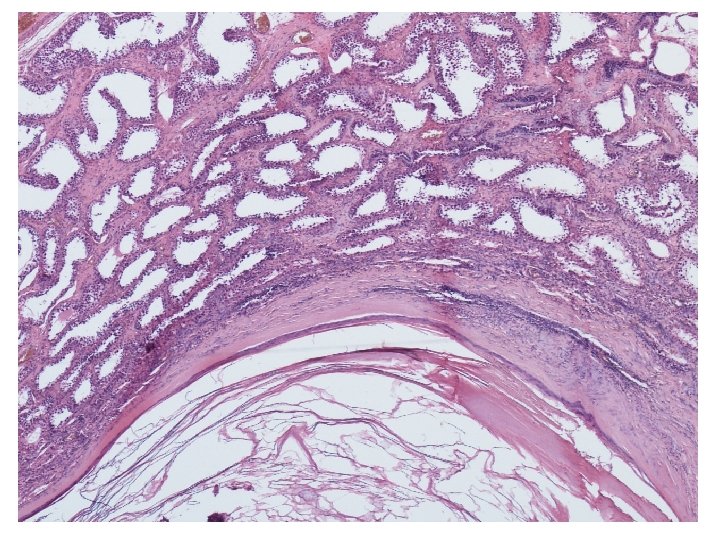

Mikroskopické vyšetření • tkáň varlete se stěnou cysty tvořenou různě silným hyalinizovaným vazivem s různě intenzivní kulatobuněčnou zánětlivou celulizací, která je ložiskově vystlaná zachovalým rohovějícím vrstevnatým dlaždicovým epitelem • v lumen cystického útvaru keratinové hmoty • v okolí cystického útvaru atrofické a hyalinizované semenotvorné kanálky

teratom prepubertálního typu (nezávislý na intratubulární germinální neoplázii), tzv. epidermální cysta